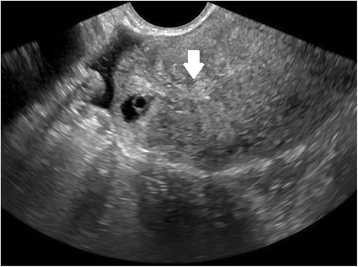

Ultrasound criteria for diagnosis of an interstitial ectopic pregnancy include a gestational sac at least 1 cm lateral to the edge of the uterine cavity, with a thin (5 mm or less) layer of overlying myometrium surrounding it (Figs. 3 and 4) [99, 100]. An ‘interstitial line’ may also be seen (Fig. 5) [101].

Interstitial ectopic pregnancy by transvaginal ultrasound. The arrow indicates thin (<5 mm) myometrium overlying the ectopic pregnancy. This finding by ultrasound, in combination with the lateral location of the gestation, has a reported specificity of 88-93 % but a sensitivity of just 40 % [101].